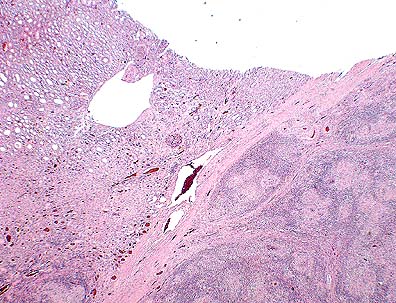

Marked dermal inflammatory infiltrate, most prominent in perivascular and periadnexal areas, in the ear of a steer infected with capripox ("lumpy skin disease".) (HE, 100X, 50K)

Necrotizing vasculitis in the ear of a steer infected with capripox ("lumpy skin disease".) (HE, 200X, 50K)

Grossly, the skin lesions appear as variably sized, marked, firm swellings. With time, the centers of some of the swellings will become necrotic and ulcerated, resulting in a characteristic lesion known as a "sitfast." Histologically, the skin lesions are very distinct and share features in common with the other capripoxviruses, i.e. sheep pox and goat pox. There is often a striking paucity of epidermal changes. The dermis is edematous, cellular, and occasionally infarcted. Scattered throughout the inflammation are variable numbers of "sheep pox cells" - histiocyte-like cells with large vacuolated nuclei and poorly-defined eosinophilic cytoplasmic inclusions. In addition to skin, these "sheep pox cells" may be seen in other tissues altered by the virus such as nasal turbinates, trachea, and lung.

Subcutaneous or intradermal inoculation of LSD virus results in the development of localized swelling at the site of inoculation after four to seven days and enlargement of the regional lymph nodes. Generally, eruption of skin nodules occurs 7 to 19 days post-inoculation. Viremia occurs after an initial febrile period and persists for about four days. A variety of cell types, including epithelial and endothelial cells, pericytes and fibroblasts are infected by the virus. Vasculitis can result from viral infection of endothelium, pericytes and probably other cells in blood and lymph vessels. Infarction may occur in severe infections. LSD virus is present in skin nodules, normal appearing skin, lymph nodes, liver, kidneys, skeletal muscle, saliva, and semen of infected animals.